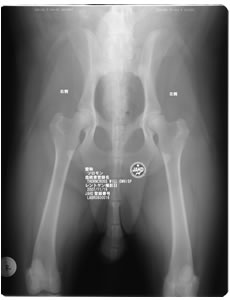

ソロモンの股関節評価

ソロモンの股関節評価 0/1 総スコア 1

100%明らかに関節炎の所見が認められないと診断されました。